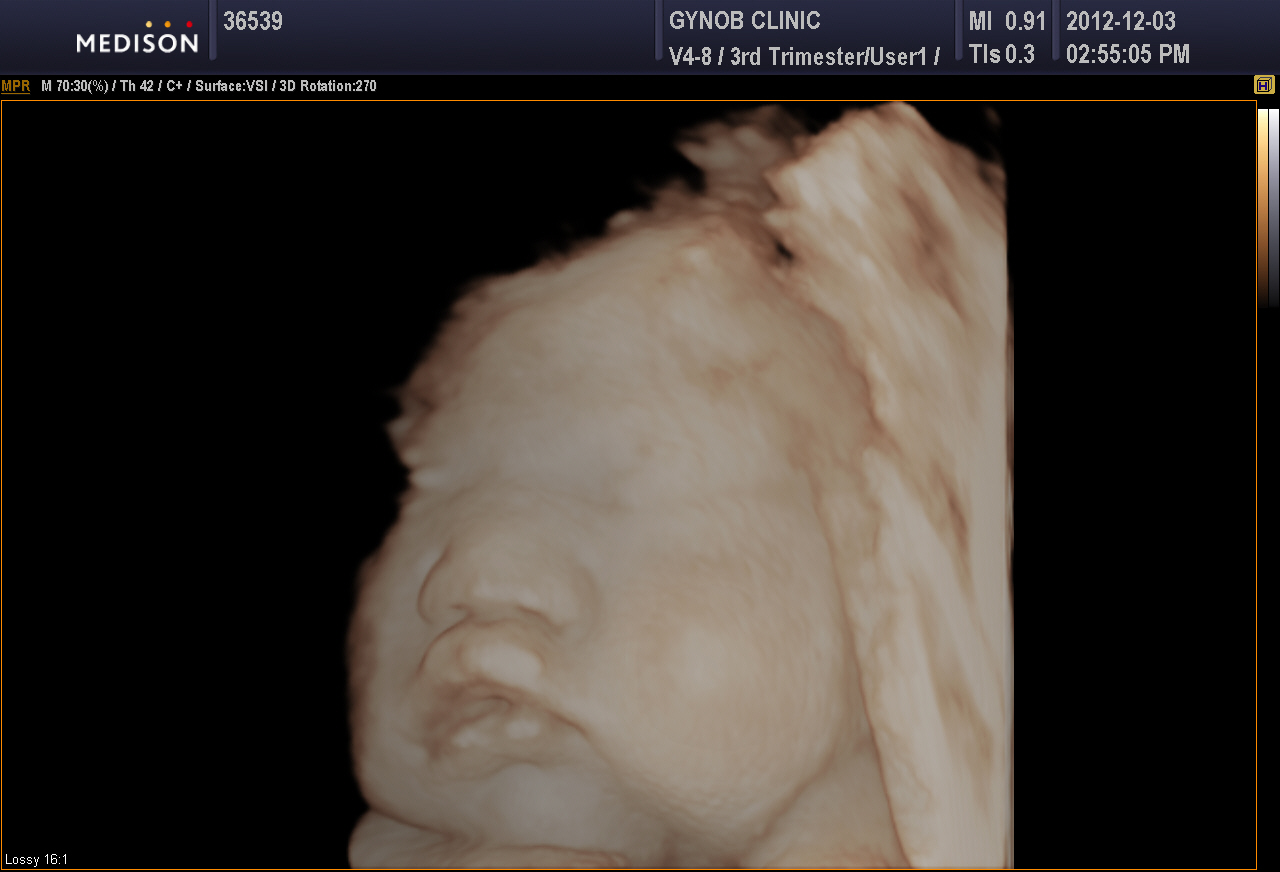

초음파 사진

날짜: 2012년 12월 3일